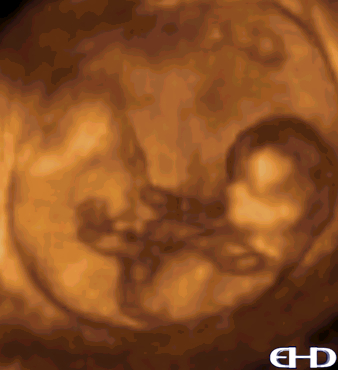

8 Week 3d Ultrasound

8 week 3d ultrasound. 8 WEEK ULTRASOUND HEARTBEAT 8 weeks 3 days. This ultrasound was done today 7313. Estimated gestational age 86 based on morphological characteristics.

The outer ears would be starting to form. During 8 week 3D ultrasound youll see the organs more clearly. Your ultrasound says GA 11w2d in the top left corner which means gestational age 11 weeks 2 days.

At the 8 week scan your baby starts showing arms and legs and sometimes you can even see movements during the ultrasound. This is what the embryo looks like at 8 weeks. Your eight-week ultrasound offers a great deal of information about a pregnancy including placenta and embryo size and strength of the heartbeat and umbilical cord.

Below are annotated images of fetus at 8 weeks gestation imaged ex-vivo using 3D ultrasound imaging with CrystalVue and RealisticVue applied CRL. According to the 8 week ultrasound the embryo would be the size of a raspberry weighing 004 ounces and measuring about 063 inches. 3D ultrasound picture of baby at 8 weeks pregnant.

The embryo would measure 23 cms from crown to rump. Its amazing to be able to see the flicker of babys heartbeat. The eyes would have migrated from the sides to the front.